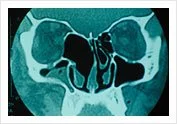

Thorough evaluation of CT Scans are essentials

Final evaluation after failure of maximal medicinal treatment with CT Scans of the sinuses being examined. The extent of surgery and inherent variations of anatomy are assessed pre-operatively. Risks are minimised by proper evaluation of the CT Scans pre-operatively to identify danger areas in the patients anatomy.

Blocked Osteo-Meatal Complex Before Surgical Treatment of Chronic Sinusitis

Scan before operation Mucocele in Ethmoid

An ethmoidal mucocele (collection of thick fluid in a sinus cavity) causing exophthalmos (bulging of the eyeball).